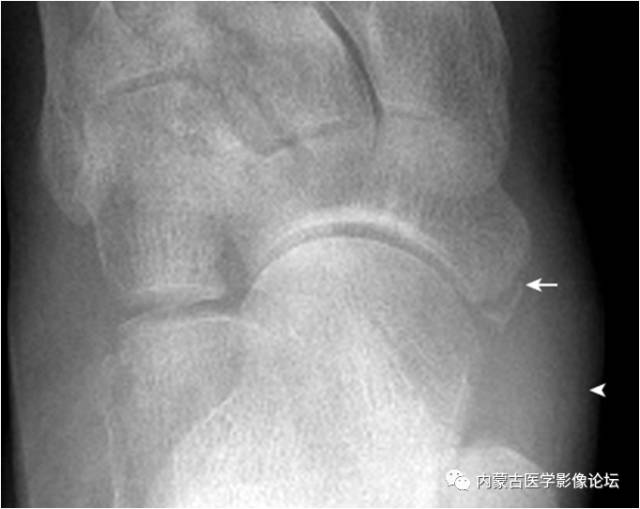

27.舟状骨粗隆撕脱骨折:舟状骨粗隆后见游离小骨片(箭),与外胫骨及腓小骨的鉴别点在于骨片前缘模糊,无硬化缘,且与粗隆有较好的对合关系,同时邻近软组织明显肿胀(箭头)。